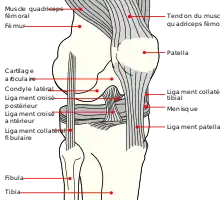

La patella s’articule en arrière avec l’extrémité inférieure du fémur appelée la surface patellaire du fémur, formant l’articulation fémoro-patellaire. Elle joue un rôle important dans le mouvement d'extension et de flexion du genou.

La patella, triangulaire en vue supérieure, possède une crête médiane s'articulant avec le rail formé par la surface patellaire (ou trochlée fémorale en ancienne nomenclature) de l'extrémité distale du fémur.

Lors de la flexion du genou, la patella glisse dans ce rail et descend vers l'extrémité distale du fémur.

Lors de l'extension, elle remonte de la même façon. Cependant le valgus physiologique crée une tendance à une subluxation externe de la patella. La patella est stabilisée par l'insertion des fibres horizontales du muscle vaste médial et par la proéminence du condyle latéral du fémur, qui empêche la luxation latérale lors de la flexion. Les fibres rétinaculaires de la rotule la stabilisent également pendant l'effort.

La patella est reliée au tibia par le puissant tendon patellaire (anciennement tendon rotulien) qui prolonge le tendon du muscle quadriceps fémoral.